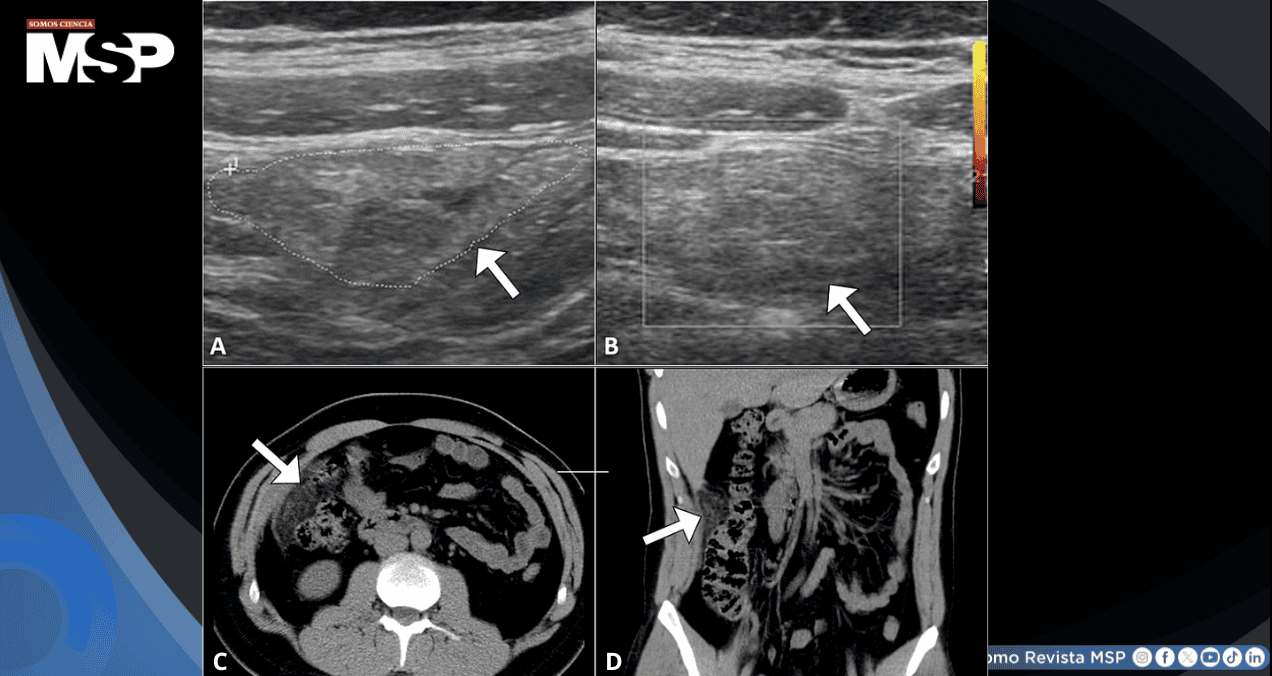

La ecografía abdominal inicial no logró visualizar el apéndice, pero identificó un área focal de hiperecogenicidad en la grasa omental del cuadrante inferior derecho, coincidiendo con el punto de máximo dolor a la palpación. El estudio Doppler color no demostró flujo sanguíneo en dicha región. No se evidenciaron alteraciones en vesícula biliar ni en el sistema urinario.

Ante los hallazgos no concluyentes, se procedió a realizar una tomografía computarizada abdominal. Este estudio demostró un área focal de densificación de la grasa en el omento mayor con una región central de hipoatenuación en la región intrahepática del cuadrante superior derecho, acompañada de engrosamiento peritoneal. Significativamente, el apéndice presenta características normales, descartando apendicitis aguda. Estos hallazgos confirmaron el diagnóstico de infarto omental agudo.